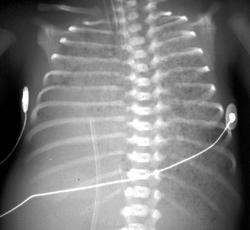

Секвестрация легкого

На компьютерных томограммах в заднемедиальном отделе нижней доли левого легкого виден участок повышенной воздушности, легочный рисунок в нем деформирован, не прослеживаются просветы сегментарных бронхов, нет дренирующего бронха.

"Секвестрированный" участок в заднемедиальном отделе нижней доли левого легкого кровоснабжается аномальной артерией, отходящей от аорты.